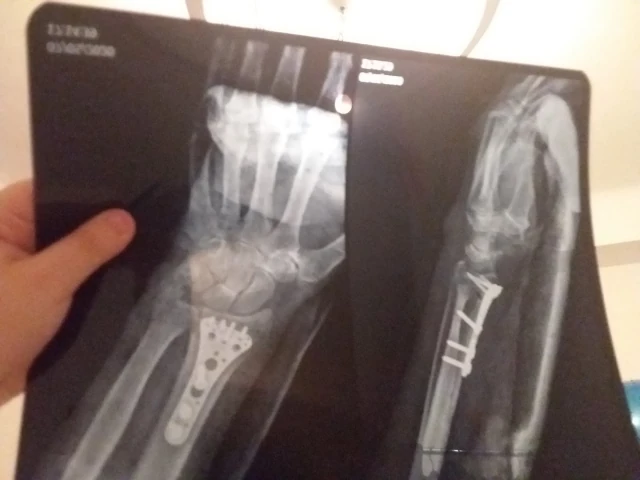

Ostéosynthèse de fracture de l'extrémité distale d'un os de l'avant-bras, à foyer ouvert

Ostéosynthèse de fracture ou de décollement épiphysaire de l'extrémité distale d'un os de l'avant-bras par broche, à foyer fermé

Réduction et fixation de fractures

Réparation de traumatismes musculo-squelettiques

Fracture

Fractures osseuses